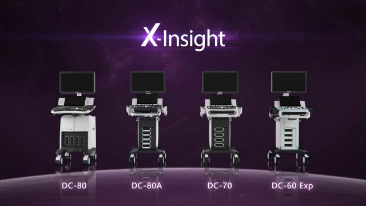

DescripciĂłn general

X-Insight es la soluciĂłn inteligente para un mejor diagnĂłstico.

La nueva soluciĂłn de Mindray es una excelente transformaciĂłn desde la continua comprensiĂłn de las necesidades clĂnicas del usuario, combinada con la evoluciĂłn de la tecnologĂa de los ultrasonidos mĂĄs puntera.

BasĂĄndose en una profunda comprensiĂłn de las necesidades del usuario, el DC-70 con X-Insight estĂĄ dise?ado para ofrecer una alta eficiencia con imĂĄgenes de precisiĂłn, la cual se ve potenciada por una eXpress Clarity, eXceptional Intelligence, eXceeding Experience.